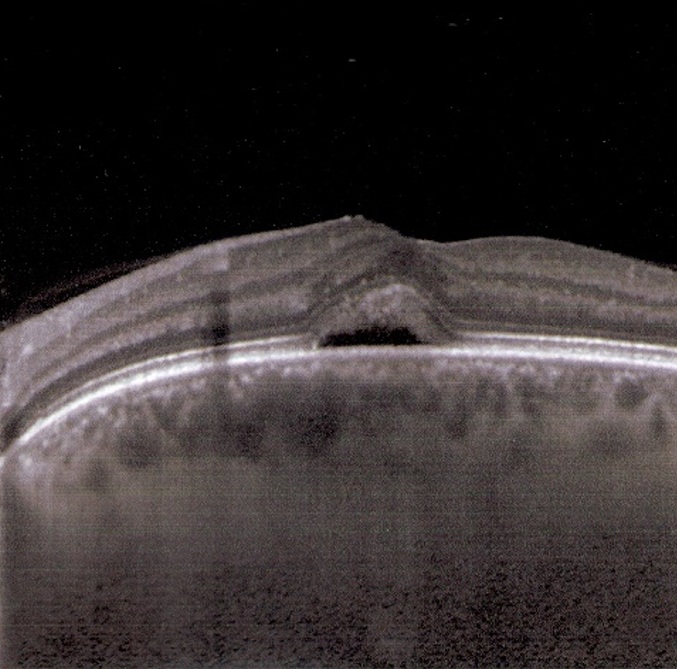

29. Hao S, Hao W, Ma Y. The features of serous retinal detachment in preeclampsia viewed on spectral-domain optical coherence tomography. Pregnancy Hypertens. 2024 Jun;36:101117. doi: 10.1016/j.preghy.2024.101117. Epub 2024 Feb 29. PMID: 38428345.

3. Rashidian P, Karami S, Salehi SA. A review on retinopathy of prematurity. Med Hypothesis Discov Innov Ophthalmol. 2025 Feb 1;13(4):201-212. doi: 10.51329/mehdiophthal1511. PMID: 40065804; PMCID: PMC11890260.